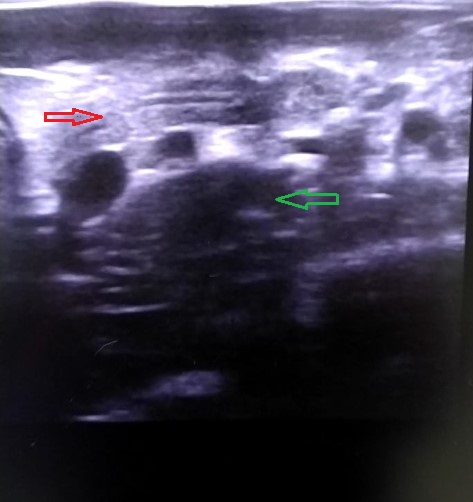

На УЗИ выявлено увеличение лимфатического узла в проекции подвздошной кишки-контуры не ровные, без изменения структуры, со снижением эхогенности (Рис. 1 и Рис 2.). Локальный оментит, илеит со снижением перестальтики, дифузное изменение паренхимы печени. Важно, что другие лимфоузлы и селезенка были без изменений.

Рис 2. Поджелудочная железа-красная стрелка. Изменённый лимфатический узел-зеленая стрелка.